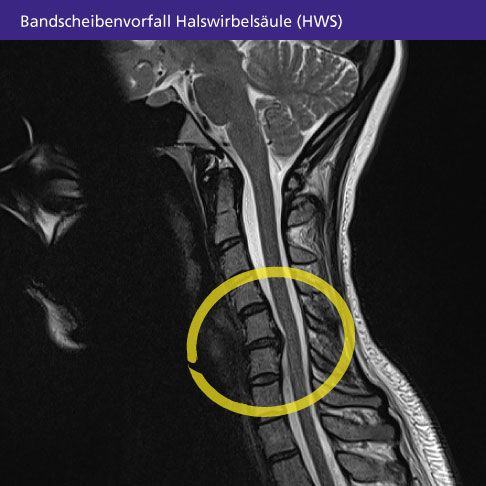

Bei einem Bandscheibenvorfall der Halswirbelsäule (HWS) tritt Material aus dem inneren Gallertkern einer Bandscheibe im Halsbereich durch den umhüllenden Faserring nach außen. Es drückt auf das Rückenmark oder die Rückenmarksnerven (Spinalnerven) in einem bestimmten Abschnitt der Halswirbelsäule. Die Quetschung der Nerven löst die für einen HWS-Bandscheibenvorfall typischen Symptome aus: starke Nackenschmerzen, Arm- und Schulterbeschwerden.

Ergänzend fertigt der Arzt eine Röntgen-, CT- oder MRT- Aufnahme an, um das Ausmaß und die Ausrichtung des HWS-Bandscheibenvorfalls gut beurteilen zu können. In seltenen Fällen kommt eine Myelographie zum Einsatz. Mithilfe einer Injektion von Kontrastmittel in den Wirbelkanal kann der Arzt die Kompression des Spinalnervs sowie die Lage des Vorfalls exakt auswerten und seine Behandlung darauf abstimmen.

Der behandelnde Arzt wird schnellstmöglich bildgebende Untersuchungen durchführen. Sieht er im MRT oder Röntgen einen massiven Bandscheibenvorfall mit deutlicher Kompression des Rückenmarks, wird er mit Ihnen über die Möglichkeiten einer operativen Therapie sprechen.